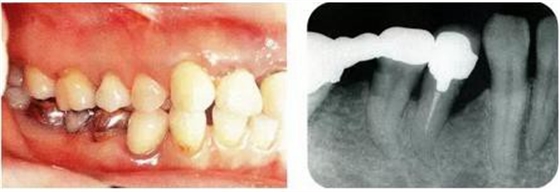

圖18-1(左),2 (右)▲初診時(shí)口腔內(nèi)照片和X線片,右下4近中有較深的1壁性骨缺損,右下45有根接近。如果在這個(gè)情況下進(jìn)行骨外科處理,需要犧牲較多的右下3遠(yuǎn)中的牙槽骨。也會(huì)造成周圍骨形成較大的臺(tái)階。